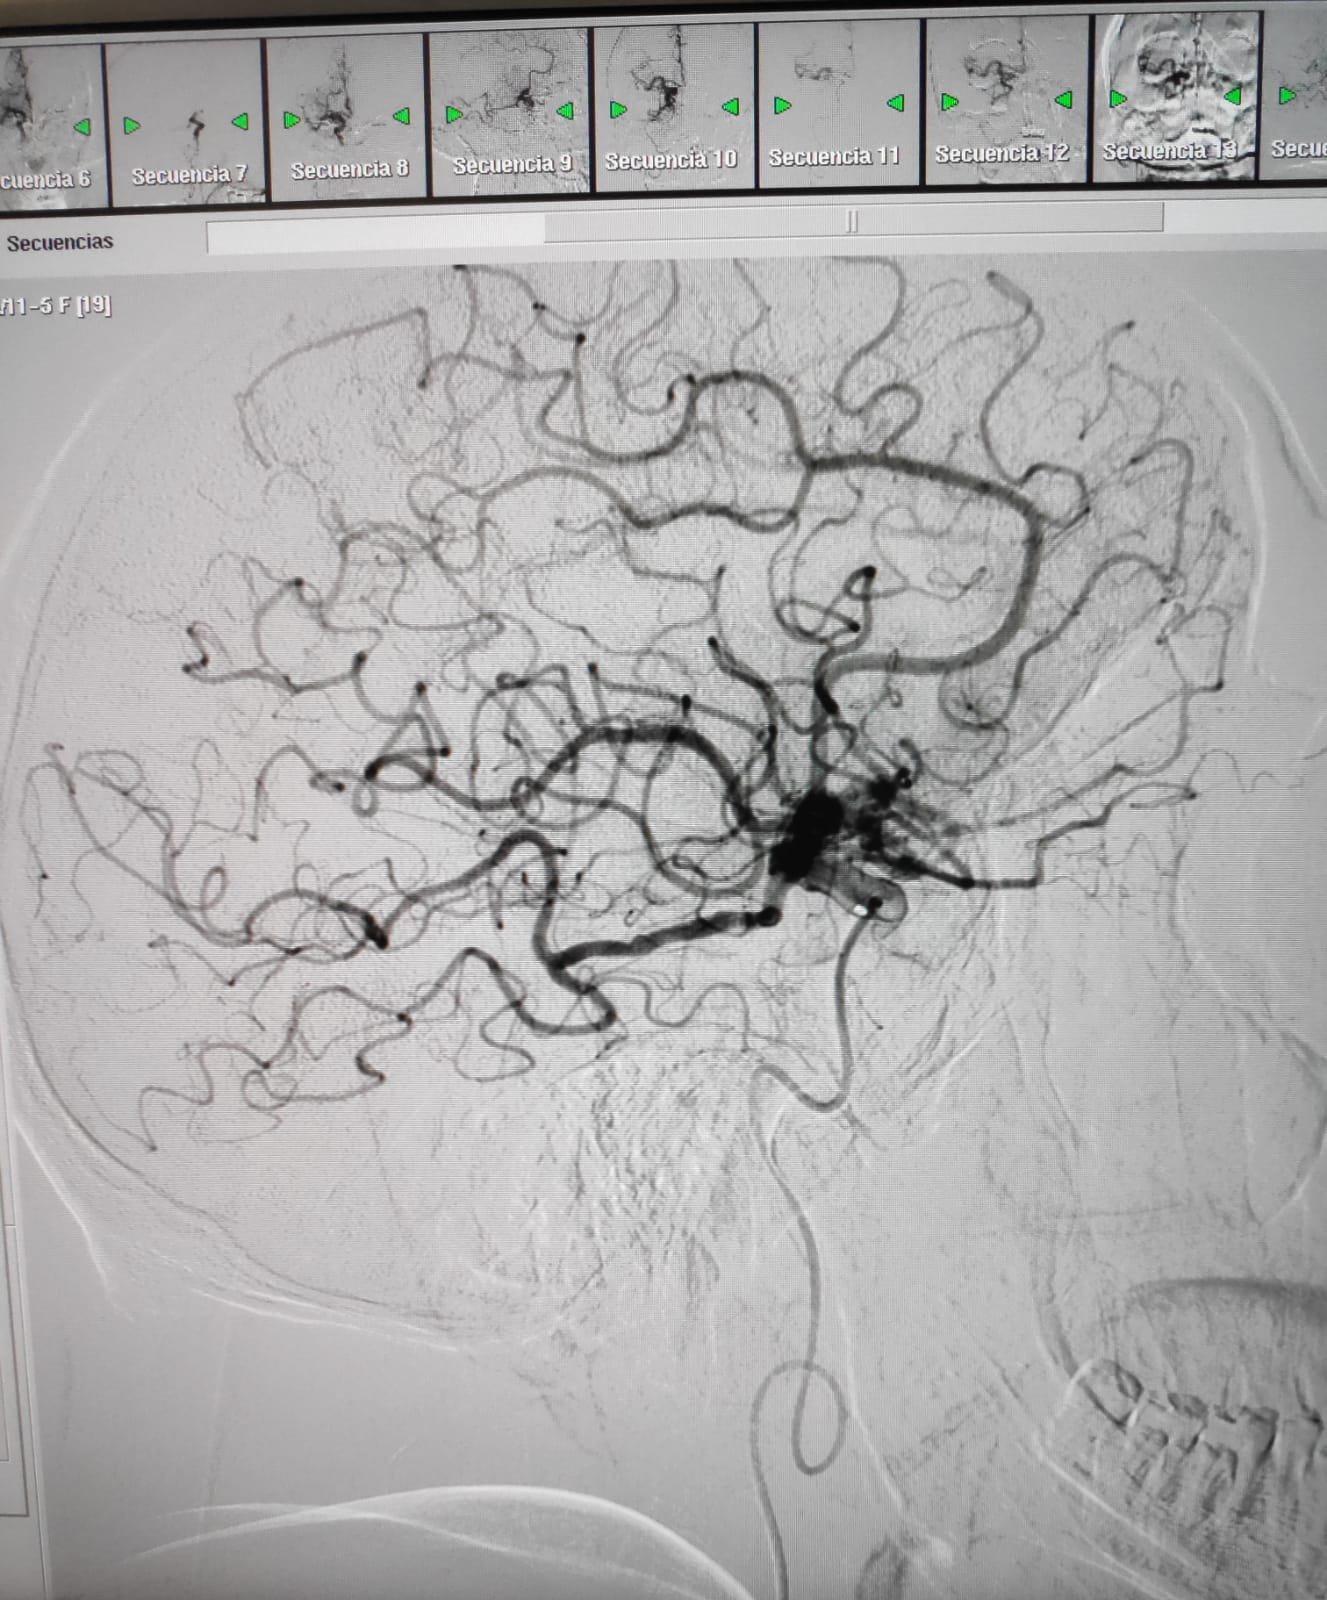

La sala de radiologia intervencionista durant la realització d'una trombectomia mecànica a un pacient que havia patit un ictus isquèmic.

En aquestes dues imatges, podem veure com queda afectada la circulació arterial arran d'un ictis isquèmic i com es recupera després del tractament endovascular.